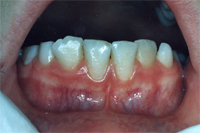

Ein 31 Jahre alter Patient zeigt einen starke Zahnfleisch-Rückgang im Oberkiefer (Abb. 1 und 3) und wir beschliessen, diese Rezessionen zu behandeln.

Der Erfolg der Behandlung ist deutlich in den Abb. 2 und 4 zu sehen. Sehr augenfällig konnte die Situation um den Eckzahn im linken Oberkiefer verbessert werden (vergleiche dazu Abb. 3 vorher und Abb. 4 nachher).